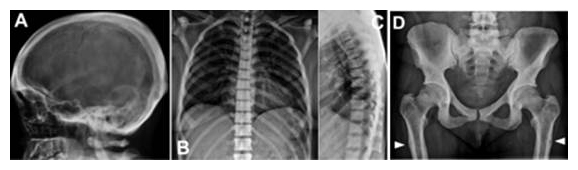

頭蓋骨、脊椎、骨盤、大腿骨の骨濃度の増加が見られる、Ikegawa型大理石骨病患者のX線像

図1 Ikegawa型大理石骨病のX線像

新たなタイプの大理石骨病(Ikegawa型大理石骨病)患者のX線像。A:頭蓋骨は幅が厚い。B, C:脊椎は一様に骨濃度が上昇している。D:骨盤、大腿骨の骨濃度の増加。白矢印は、大腿骨の偽骨折。E: 手の短管骨の皮質は幅が厚い。